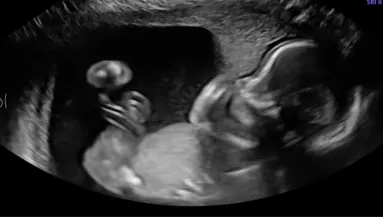

Nem mindennapi történet bukkant fel a Tik-Tok-on: az Edinburgh-ban élő Sarah-Jayne Snowkétségbeesetten kéri a viág segítségét, mert szeretne metalálni egy fiatal férfit, akivel tavaly a nyaralásán bújt ágyba. Rövidesen ugyanis anya lesz. "Ismeri valaki ezt a glasgow-i fickót?" - kérdezte a nyolcadik hónapban lévő nő a Tik-Tok videójában, amit már több mint kétmillióan néztek meg. Majd a részletekre is fény derült: tavaly augusztusban a Kanári-szigeteken ismerték meg egymást, egyetlen éjszakát töltöttek együtt.

"A srácnak, akivel Tenerifén találkoztam (...): Apa leszel 2023 áprilisában" - szól a lány egyértelmű üzenete.